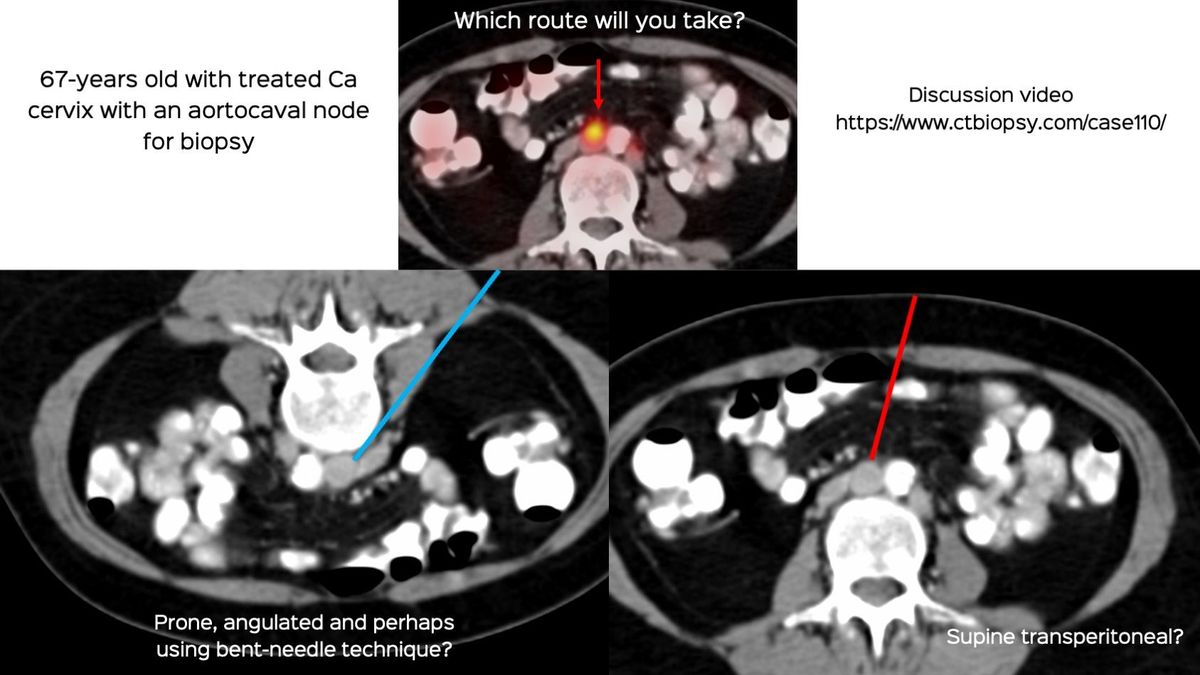

A similar biopsy was described as Case 110 here.